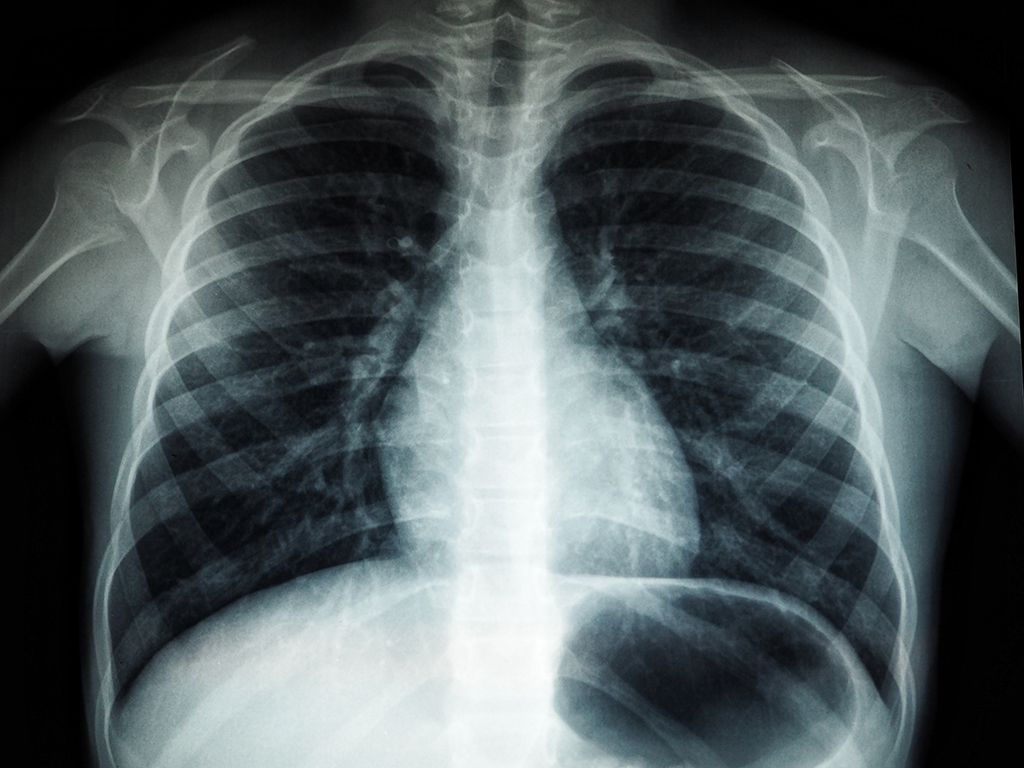

A patient mystery I never understood was a healthy 23-year-old male. He came into the ER with chest pain that started after eating something spicy.

We check his vitals, do an X-ray, and are about to discharge him when he collapses lifeless. We start CPR and get a pulse. He was stable for a CT scan but doesn’t survive the procedure.

The team was baffled. During the autopsy, it was revealed his major blood vessels basically just imploded. This sometimes, though rarely, happens to men in their 70s with a long smoking history and high blood pressure, but this patient had zero risk factors and was a non-smoker.